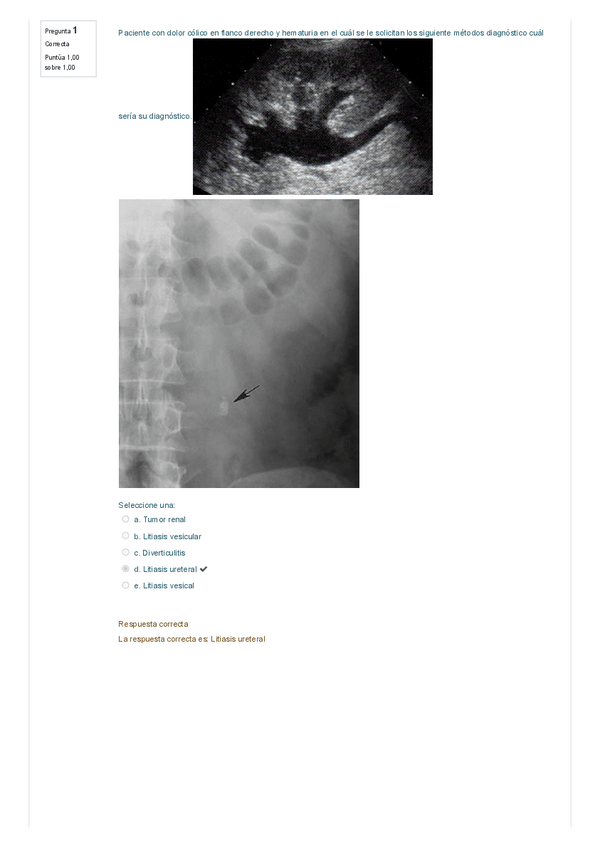

Examen Práctica abdomen

20 páginas